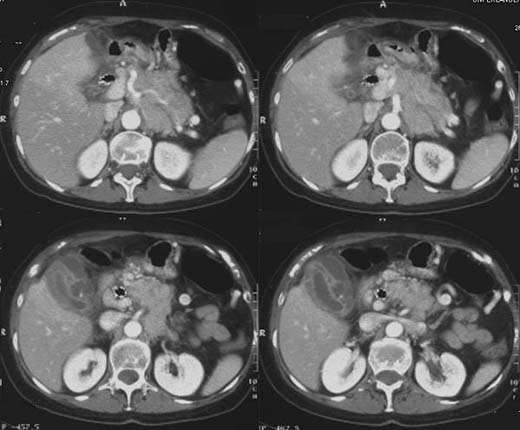

CT-Abdomen

nach i.v. und oraler Kontrastmittel-Gabe.

Um die wandverdickte kontrastmittelaufnehmende

Gallenblasenwand mehrere zum Teil liquide,

zum Teil septierte

randständige kontrastmittelaufnehmende Formationen.

Perforierte

Gallenblase mit Abszessbildung auf dem Boden einer akuten Cholezystolithiasis.